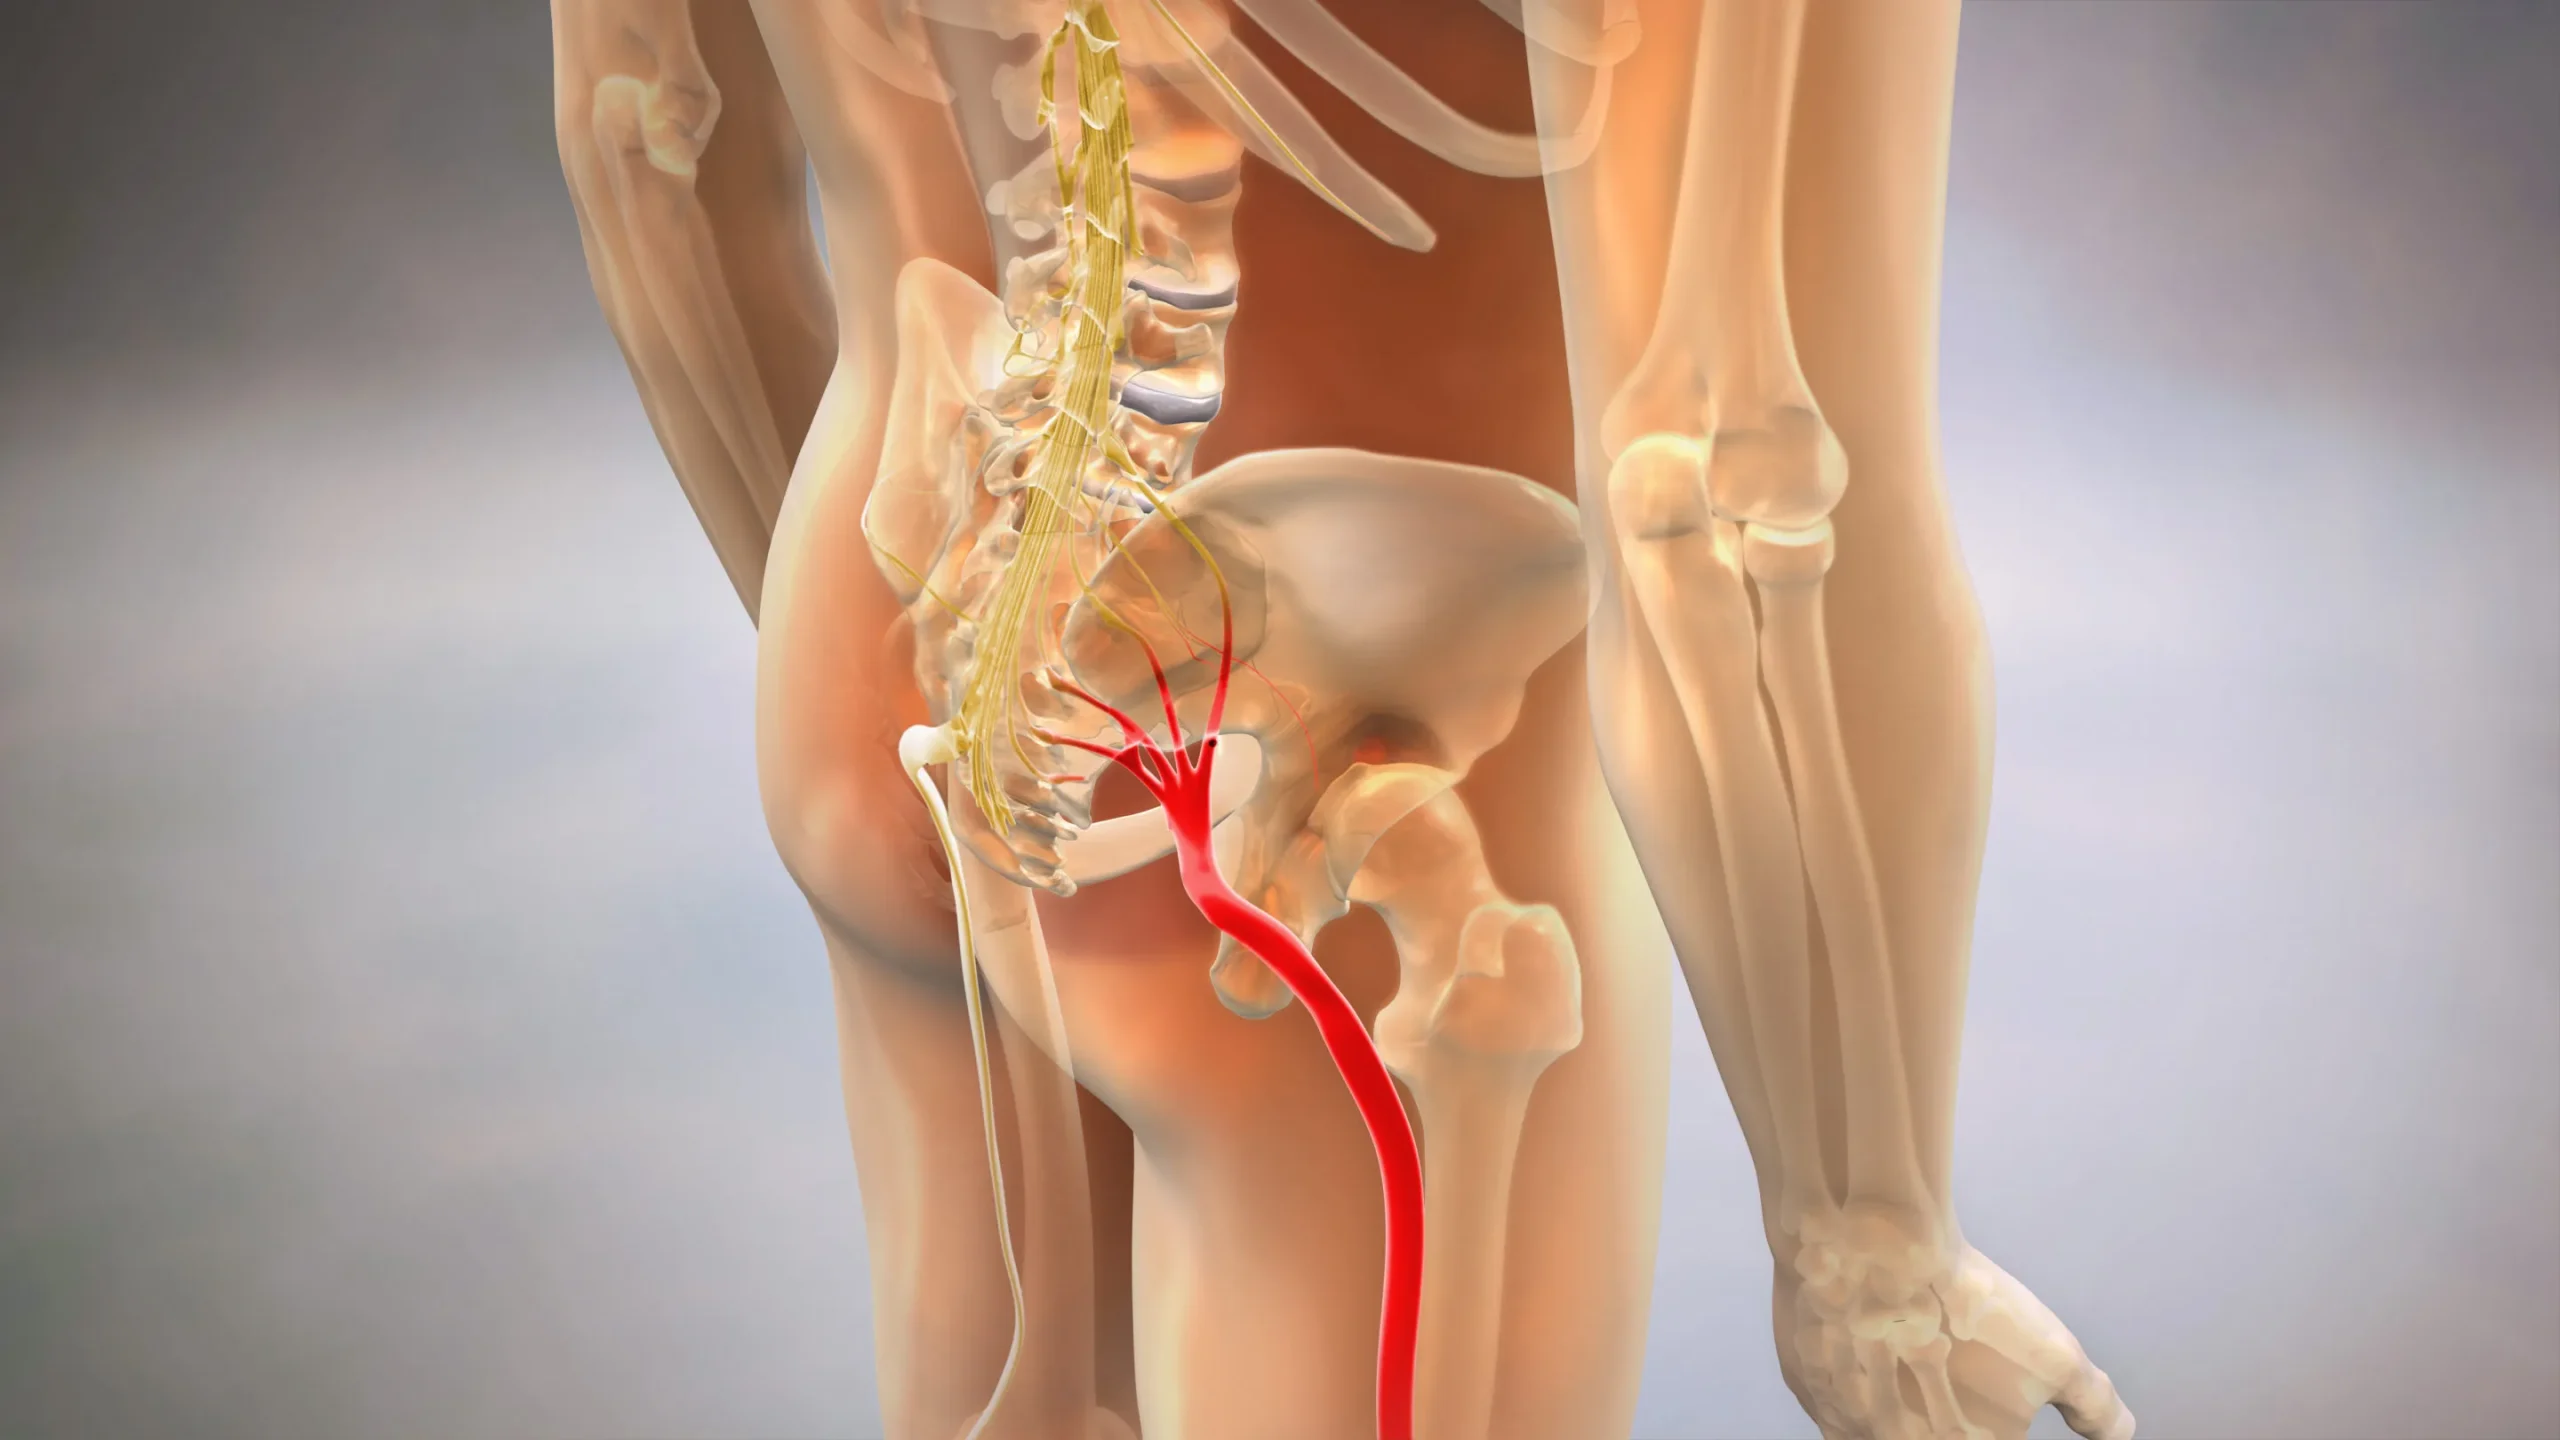

سیاتیک (Sciatica) در واقع نام یک بیماری خاص نیست، بلکه به مجموعهای از علائمی گفته میشود که بر اثر فشار یا تحریک عصب سیاتیک به وجود میآید. عصب سیاتیک طولانیترین و ضخیمترین عصب بدن است که از پایین کمر شروع میشود، از میان باسن عبور میکند و تا ساق و کف پا ادامه دارد. وقتی این عصب تحت فشار قرار بگیرد. معمولاً بهدلیل دیسک کمر، تنگی کانال نخاعی یا اسپاسم عضله پیریفورمیس در باسن، درد شدیدی از ناحیه کمر به پا تیر میکشد.

درد سیاتیک معمولاً بهصورت درد سوزشی، تیرکشنده یا شوکمانند احساس میشود و اغلب فقط در یک پا بروز میکند. این درد ممکن است با علائمی مانند گزگز، بیحسی یا ضعف عضلانی در پا همراه باشد و در حالتهایی مثل نشستن طولانیمدت، خم شدن یا سرفهکردن تشدید شود. در موارد شدید، حتی راهرفتن یا ایستادن هم دشوار میشود.

نکته مهم این است که سیاتیک معمولاً نتیجه یک بیماری زمینهای مانند فتق دیسک کمر است، نه اینکه خودش یک بیماری مستقل باشد. به همین دلیل، برای درمان سیاتیک باید علت اصلی فشار بر عصب مشخص و برطرف شود. اگر میخواهید بیشتر درباره علائم و روشهای درمان این عارضه بدانید، پیشنهاد میکنیم مقاله سیاتیک چیست؟ و همچنین مقاله روش های درمان سیاتیک را مطالعه کنید تا ارتباط میان دیسک و درد سیاتیک را بهتر درک کنید.

در فتق دیسک، بخشی از دیسک بینمهرهای پاره میشود و مادهی ژلهای داخل آن به بیرون نشت میکند. اگر این ماده به یکی از ریشههای عصبی که از نخاع خارج میشود فشار بیاورد، مخصوصاً ریشههایی که منتهی به عصب سیاتیک هستند، فرد دچار درد تیرکشنده در پا میشود و این یعنی سیاتیک. به زبان سادهتر، دیسک کمر میتواند علت سیاتیک باشد، اما سیاتیک خودش علت دیسک کمر نیست.

در دیسک کمر، درد معمولاً در ناحیه پایین کمر متمرکز است و گاهی تا پا انتشار پیدا میکند. در مقابل در سیاتیک درد معمولاً از باسن شروع میشود و به صورت تیرکشنده تا پشت ران، ساق و حتی کف پا ادامه مییابد. این درد ممکن است با بیحسی، گزگز یا ضعف در پا همراه باشد و هنگام نشستن طولانیمدت، سرفه یا عطسه شدیدتر شود.